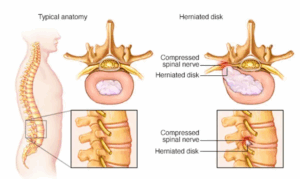

Slipped disc

A herniated disk refers to a problem with one of the rubbery cushions, called disks, that sit between the bones that stack to make the spine. These bones are called vertebrae.